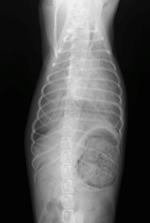

症例3

プロフィール:セキセイインコ、2才、雌。

主訴:お腹が膨らんで苦しそうにしている。

身体検査所見:腹部の膨満と硬結感を認める。

X線検査所見:腹腔内に卵殻を伴った卵を認める。

評価:卵塞。ガス麻酔下にて用手排卵を実施し卵を排出。麻酔の覚醒は良好であった。